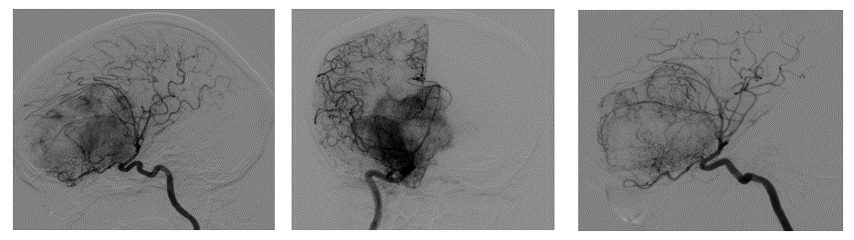

Figura 1. Imágenes de RM .Gran masa extraaxial con espolón enostótico en planum sphenoidale que englobe posteriormente las apófisis clinoides y se extiende por las alas mayores del esfenoides. Tras la administración de contraste presenta realce intenso y homogéneo. Condiciona marcada deformidad de la porción anterior del cerebro, herniación transtentorial descendente con herniación de tercer ventrículo hasta la cisterna prepontina.

Silla turca vacía, encefalocele de ápex petroso derecho y marcada ectasia de vainas de nervios ópticos con protrusión de las cabezas en globos oculares.